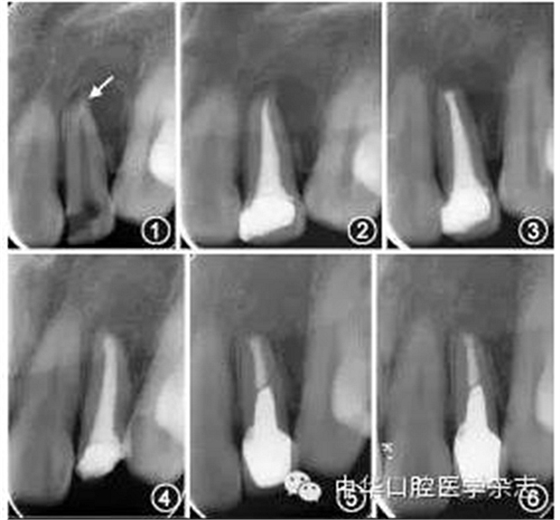

常用的非手術(shù)治療方法包括采用顯微超聲技術(shù)從根管內(nèi)取出分離器械、在分離器械側(cè)方形成旁路通過、或?qū)⒎蛛x器械保留于根管內(nèi)作為部分根充物。對于非手術(shù)治療無法取出分離器械的病例,若根管內(nèi)殘余感染導(dǎo)致癥狀持續(xù)或加重,在充分評估療效和風(fēng)險后可以考慮行顯微根尖手術(shù),圖1~6為1例顯微手術(shù)處理根尖段分離器械的病例,術(shù)后31個月復(fù)查顯示根尖愈合良好。術(shù)前拍攝錐形束CT可以獲得分離器械位置、根尖炎癥范圍、術(shù)區(qū)與鄰近重要解剖結(jié)構(gòu)間的距離等信息;術(shù)中暴露根尖后,根據(jù)分離器械的位置和長度,可以將分離器械與根尖一并截除,或切除根尖后取出器械。

圖1 術(shù)前根尖X線片示22根尖段分離器械(箭頭)伴根尖周陰影 圖2 22完成根管治療,分離器械暫未處理 圖3 22顯微根尖手術(shù)后根尖X線片示根尖切除和倒充填,術(shù)中已去除分離器械 圖4 術(shù)后14個月復(fù)查,22根尖陰影較術(shù)前縮小 圖5 術(shù)后16個月復(fù)查,22根尖陰影進(jìn)一步縮小,完成冠修復(fù) 圖6 術(shù)后31個月復(fù)查,22根尖愈合良好